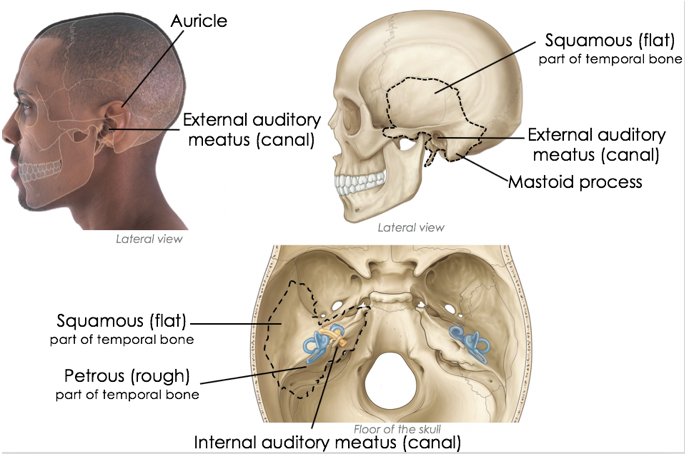

The external ear can be divided functionally and structurally into two parts. What are they?

- Auricle (or pinna)

- External acoustic meatus

In the middle of the auricle is a hollow depression. What is it called? What does it continue into the skull as?

Concha - continues into the skull as the external acoustic meatus

Function of the concha/auricle?

funnels sound waves into the ear canal via the external acoustic meatus